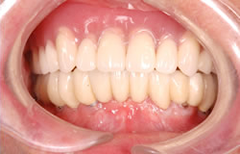

下顎の無歯顎に8本のインプラントを埋入して咬み合わせを作った症例

下顎全顎にインプラント埋入(8本)後、セラミックの歯を装着し、上顎は総義歯をいれた。

約7年経過後も問題はございません。